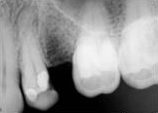

antes depois